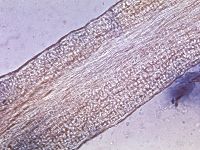

KOH-preparaat en schimmelkweek. Nadeel is dat het kweken tot drie weken kan duren, voordat de schimmel gedetermineerd kan worden. De diagnostiek wordt bemoeilijkt wanneer de patiënt al behandeld wordt met lokale antimycotica. T. tonsurans is een endothrix groeiende schimmel, dit kan soms worden gezien door een KOH preparaat van de haren te maken (kost wel tijd, moet lang liggen). Bij de endothrix groeiwijze past een klinisch beeld van kale plekken met korte afgebroken haarstompjes, te herkennen als puntjes (black dot type tinea capitis), en een negatieve fluorescentie bij onderzoek met de Wood's lamp.

Endothrix groeiwijze schimmel Endothrix groeiwijze schimmel

endothrix (T. tonsurans) endothrix (T. tonsurans)

Foto links: CDC Atlanta (Public Domain Image).